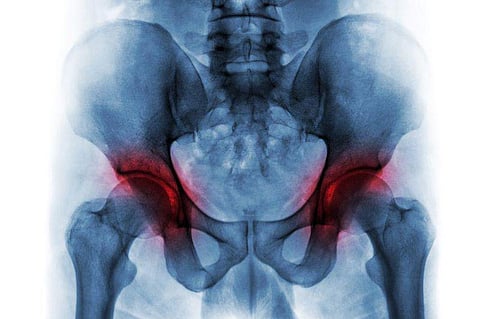

TUESDAY, Dec. 7, 2021 (HealthDay News) -- Sacral insufficiency fracture (SIF) more often occurs contralateral to total hip arthroplasty (THA) rather than ipsilateral to THA, according to a study published online Nov. 22 in the Journal of Bone & Joint Surgery.

Isabel Graul, M.D., from the University of Jena in Eisenberg, Germany, and colleagues conducted a retrospective study involving 171 patients with SIFs and identified those who had undergone unilateral THA. The rate of SIF ipsilateral and contralateral to the side of the THA was determined in patients with SIF and THA. Changes in bone mineral density at the sacral alae ipsilateral and contralateral to the THA were analyzed immediately postoperatively and at one-year follow-up in 39 THA patients with healthy bone.

The researchers found that 50 of the 171 patients with SIF were previously treated with THA. Of these, 31 were treated with unilateral THA. Overall, 13 and six patients (42 and 19 percent) had an SIF that was contralateral to and ipsilateral to the THA, respectively; 12 patients had bilateral SIFs. In the THA group without SIF, there was a significant decrease in the median bone mineral density from 35.0 to 13.0 HU at the sacral ala contralateral to the THA, while the decrease in ipsilateral bone mineral density from 24.0 to 17.0 HU was not significant.

"This leads us to conclude that THA leads to spatially different bone remodeling of the posterior pelvic ring because of altered load transmission," the authors write. "This remodeling either negatively affects the contralateral side of the sacrum (as demonstrated in the present study) or prevents natural bone loss at the ipsilateral sacrum. Additional studies focusing on this remodeling process, and assessing different implant designs and longer-term changes, are needed."